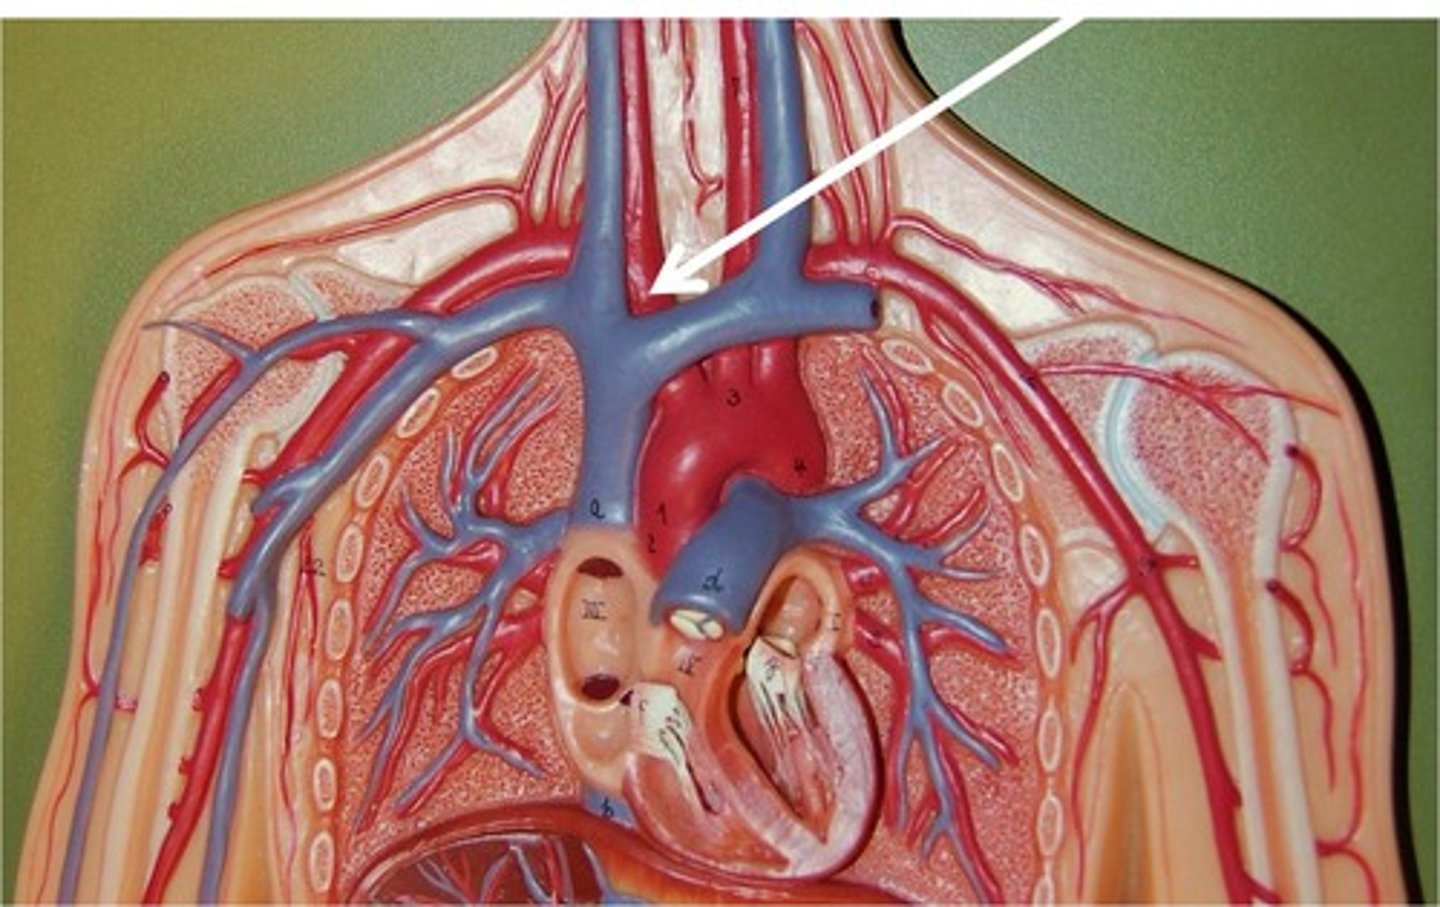

brachiocephalic vein

subclavian vein

superior vena cava